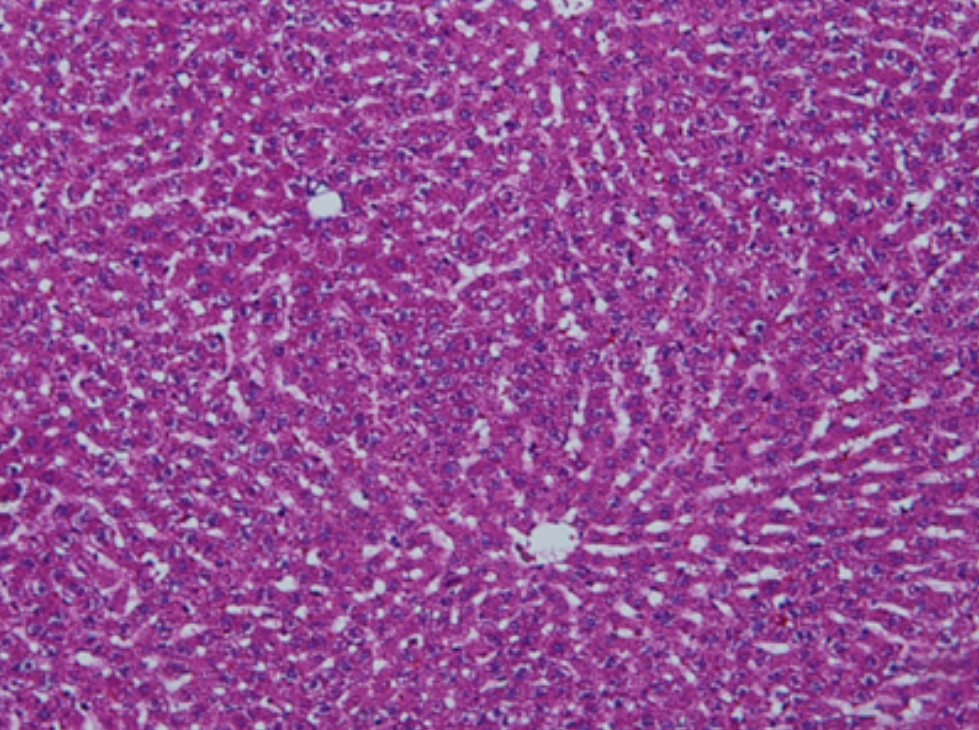

HE染色,全称苏木精-伊红染色法(Hematoxylin and Eosin staining),是最常见的组织切片染色技术之一,用于在显微镜下观察和分析组织或细胞的结构和形态。

虽然HE染色是最常见且最基础的染色技术之一,😭但在实验过程中,很容易出现各种情况导致染色切片质量参差不齐。所以,小编根据以往实验经验,给大家整理归纳出了15个HE染色中的常见问题,还包含问题原因分析以及解决方法哦~

形成原因:切片经梯度乙醇处理后没有完全脱水,导致二甲苯透明、中性树胶封固后残留大量水分。 解决方法:首先移去盖玻片,用二甲苯溶解封固剂如中性树胶,再将切片置入无水乙醇内,待切片重新脱水完全后,用二甲苯透明处理,中性树胶封固。要注意所有用于脱水和透明的液体,在使用一定时间后,应及时更换。 二、细胞核呈红、棕色 形成原因:苏木精染色液过度氧化,切片在苏木精染液染色后返蓝不足。 解决方法:每次染色之前检查苏木精染色液的染色能力,发现苏木精染色液氧化过度应及时更换。此外,切片经苏木精染色后,要给切片以足够的蓝化时间,蓝化过程可用流水、温水、弱碱性溶液(如稀氨水或0.2%碳酸氢钠)等处理。 三、切片在脱蜡后出现大片白色斑点 形成原因:由于烤(烘)片温度太低,切片上的组织蜡膜在脱蜡前没有充分烤(烘)融化。或是因为切片在二甲苯液中停留时间不足,或二甲苯使用过久,造成的脱蜡不彻底。 解决方法:若是由于切片烤(烘)温度低所致,可以先用二甲苯去除切片上的封固胶,然后重新用二甲苯脱去切片上的石蜡,再进行后续染色。若是由于切片在脱蜡的二甲苯中停留时间不足或脱蜡二甲苯使用过久浓度不足所致,则需将切片退回到二甲苯中,停留较长时间,或更换二甲苯液体重新脱蜡,再入乙醇重新脱二甲苯,入0.5%盐酸水溶液褪色后,重新HE染色。 四、细胞核苍白暗淡,即苏木精染色太淡 形成原因:切片在苏木精染色液停留时间太短;苏木精染色液过度氧化,失去染色能力,不能再继续使用;分化步骤处理时间过长;固定不及时。此外值得注意的是,若骨组织细胞核暗淡,大多是脱钙过度造成的。 解决方法:切片重新染色。如果组织在酸性固定液(如Zenker、Bouin)或非中性缓冲甲醛液固定时间过长,细胞核染色能力将减弱,需增加其在苏木精染色液的时间,或用一些方法增加组织的嗜碱性,以改善细胞核的着色。例如,上述组织玻片可以使用Weigert铁苏木精染色液。如果组织是用Zenker液固定的,可将切片脱蜡后放在5%碳酸氢钠溶液3~4h,流水冲洗5min后染色。如果组织是用Bouin液固定的,可将切片脱蜡后放在5%碳酸锂1h,流水冲洗10min后染色。 五、细胞核过染,苏木精染液占据了细胞质 形成原因:玻片在苏木精染色液停留时间过长,或是切片太厚、分化步骤时间太短。 解决方法:如果不是因为切片太厚(用显微镜仔细上下微调,只有一二层细胞核层次),就需将切片进行脱色、漂白、重新染色,适当调整染色和分化时间。但如果确定是由于切片太厚导致的细胞核过染,则需要重新切片。 六、伊红着色淡 形成原因:可能是伊红染液pH值大于5,也可能是蓝化液残留过多,切片太薄,或是切片经伊红染色后在乙醇脱水时间过长。 解决方法:检查伊红染液pH值,必要的话,用乙酸将其调节在4.6~5.0之间,从而使伊红染色色彩艳丽。此外,确保每次蓝化步骤完成后,使用的弱碱性溶液被充分洗去,玻片上没有残留的弱碱性溶液。最后,检查切片的厚度,且脱水时不要让切片在低浓度乙醇中停留时间过长,因为含水多的低浓度乙醇会将切片伊红的颜色分化掉。 七、细胞质过染、分色不足 形成原因:伊红染色液浓度太高,特别是存在焰红燃料、四溴四氯荧光素钠。切片在伊红染色时间过长,或是切片在伊红染色后经乙醇脱水步骤时时间太短,而使乙醇分化伊红的作用不能产生,都能够使细胞质过染。 解决方法:适当稀释伊红染色液,减少伊红染色时间,或使切片在乙醇脱水等步骤时,停留时间相对均匀。同样,也要检查切片的厚度是否合适。 八、切片中出现蓝黑色沉淀物 形成原因:苏木精染色液中的金属膜黏附在玻片上。 解决方法:染色前仔细过滤苏木精染色液,建议使用半氧化苏木精染色液,如Gill苏木精染色液,可以避免过多的金属膜产生。 九、光镜下切片某些区域难以聚焦 形成原因:盖玻片上可能有封固切片的封固剂。 解决方法:移去盖玻片,重新用干净的盖玻片封片。检查切片封片方法,是人工手工封法,还是机器自动封法,如有问题及时调整。 十、封固剂从盖玻片与载玻片之间的缝隙回缩 形成原因:盖玻片弯曲或不平整,或是封固剂含二甲苯过多,稀释过度。 解决方法:移去盖玻片,重新找一张盖玻片,用干净的封固剂封片。如用手工封片法,保证在封固结束时,封固剂容器盖子为紧闭状态。且尽量使用小的容器盛装封固剂,一旦封固剂太黏稠,就可以选择废弃。 十一、细胞核呈灰蓝状态 形成原因:可能由于组织处理温度过高、过热,在液体石蜡中停留的时间过长。或是固定时间太短后,直接在高浓度的乙醇中进行了脱水处理。 解决方法:理论上来说,仅在组织浸蜡步骤才进行加热,组织不能在热蜡液中停留太久。如果由于某些原因不能进行下一步包埋处理,可将组织连同塑料包埋盒一并放置在室温空气中,冷却凝固,以备包埋。待需要包埋时再重新加温直至石蜡融化即可。组织在处理前必须确保固定良好,脱水最好能从低浓度的乙醇开始。 十二、类色素的点状结晶和黑色光滑细胞核 形成原因:这种裸核改变是因为切片封片前放置在空气中的时间太长,以至于二甲苯挥发,切片干燥。 解决方法:移去组织切片上的盖玻片和封固剂,重新处理。将切片水洗数分钟,然后重新脱水、透明、封固。封片过程中要保持组织切片的轻度湿润,尽量不要让其干燥。 十三、染色过淡或过浓 解决方法:如果染色过淡,可以增加染色剂的浓度、延长染色时间或更换新鲜的染色剂;如果染色过浓,则应减少染色剂的浓度或缩短染色时间。 十四、切片出现叠加褶皱 形成原因:新购买的玻片洁净度不够、用镊子撑开切片时操作不够熟练未能平整伸展,或玻片表面有油脂,切片粘贴不牢。另外,烤片时间不足、烤片温度过低或切片过厚造成切片脱落,都会造成重叠或有皱褶的情况。 解决方法:新购买的玻片最好能用硫酸清洁液浸泡一晚,然后流水冲洗干净。在适宜的温度下烤片时间宁长勿短,保证有充足的烤片时间和温度。另外,切片刀要锋利,才能切出厚薄适宜的切片,保证切片不会因为过厚而脱落。 十五、组织残缺不全或有刮划痕迹 形成原因:组织残缺不全是由于切片时修整蜡块时深度不够、组织没有全部暴露于切面。切片的刮划痕迹是由于切片刀的刀锋有缺口、包埋的组织有异物,或是钙化组织、骨组织及包埋石蜡有沙粒造成的。 解决方法:修整蜡块时保证组织块全部暴露于切面,切片时保证切片刀的锋利没刀口。同时在组织取材时去除手术异物和钙化组织。最后,骨组织要完全脱钙,这样可以保证切片的完整和平整美观。 *注:由于实验中导致结果出现误差的原因多种多样,以上内容仅供参考,具体根据实际情况进行判断。